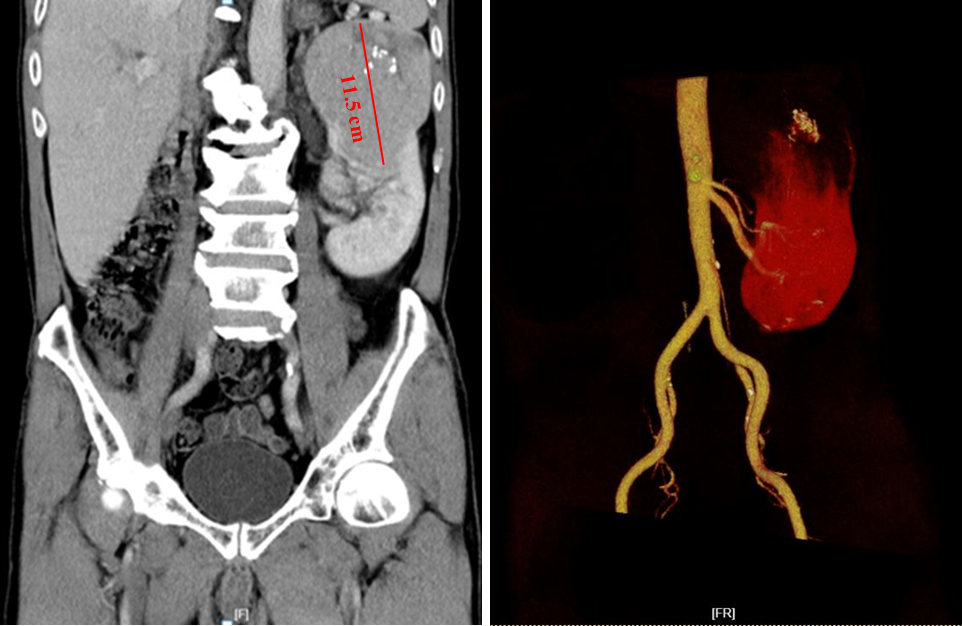

该患者为59岁男性,因体检时发现先天性右肾缺如、左肾巨大肿块慕名就诊于泌尿外科。收住院后完善CT、肾血管成像等检查,结果提示患者左肾上极有一大小约115´86´96mm巨大肿块,左肾动脉呈双支型,右肾缺(如图)。泌尿肿瘤亚专科汪金荣、姚鲲副主任医师经过综合评估后认为,患者为先天性孤立肾,有保留肾单位手术的绝对适应症,如能完整切除肿瘤,保留肾脏,可避免根治性肾脏切除导致的尿毒症及长期透析治疗,提高患者的生活质量,减轻经济负担。但考虑到该患者肿瘤巨大,且肾内侵犯较深,肿瘤下极靠近肾门处肾动脉主要分支和肾盂肾盏,要做到“拆弹”+ 保肾,手术难度大、风险高。因此,汪金荣副主任医师团队进行了详细的术前讨论、准备及沟通,制定了较优的手术方案:腹腔镜结合开放手术左肾部分切除术。该方案可避免完全腹腔镜手术肾动脉阻断时间过久引起的肾功能损害,又可减小开放手术的切口长度、减少创伤。泌尿外科肿瘤亚专科肾脏肿瘤专病护理小组为其制定个性化术前预康复指导,为手术耐受,术后快速康复提供有力保障。

患者术前CT影像